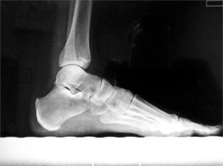

POSICION 4 : PIE LATERAL EN CARGA

Paciente en BIPEDESTACION O CARGA lateral, apoyando la cara lateral del pie sobre el cassete. El haz de rayos es dirigido verticalmente al centro del tarso.El casette en nuestro caso se coloca en el bucky y el paciente en un escalon.

CONSIDERACIONES MEDICAS Posicion 4 : PIE LATERAL EN CARGA

Lateral de pie en bipedaestacion

Posicion de gran uso en ortopedia y complementaria al perfil en decubito, es importante especificar si el apoyo es monopodalico, en patologia de sobreesfuerzo, puede ser de importancia el observar los puntos de contacto, en la medida en que los arcos plantares son respetados podremos descartar patologia mas que observarla, y no olvidar que es un enfoque complementario, algunos prefieren este enfoque para observar la medio tarsiana y su estado articular ,a veces tambien es necesario acompañar de un frente en apoyo para complementar la observacion. Dr.Aramayo